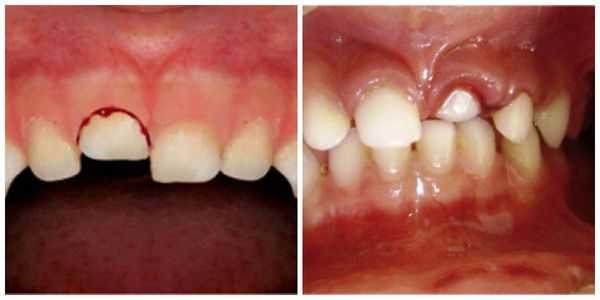

Неполный вывих

При этом виде травмы зуб может перемещаться вестибулярно, орально, окклюзионно, в сторону соседних зубов или поворачиваться вокруг своей оси. При смещении зуба в вестибулярном или оральном направлении на рентгенограмме зуб проецируется более коротким по сравнению с соседним и нетравмированными зубами из-за того, что он наклонен. Проекция зуба будет тем меньше , чем больше его наклон. Изменяется и периодонтальная щель. Когда смещение зуба незначительное, периодонтальная щель расширена только у дна альвеолы. При значительном смещении имеет место расширение у верхушки и у боковых поверхностей

корня (рис. 1) .

Иногда неполный вывих в вестибулярную сторону сочетается с отломом альвеолярного края. На рентгене это выглядит как нарушение непрерывности кортикальной пластинки, ограничивающей лунку зуба, и в губчатой кости появляется полоска просветления (рис. 2) . При вывихе в сторону окклюзионной поверхности на рентгенограмме травми рованный зуб имеет ту же длину, что и соседний нетравмированный. Верхушка корня расположена к альвеолярному краю ближе, чем у соседнего нетравмированного зуба.

Периодонтальная щель расширена у всех поверхностей корня, особенно в области дна альвеолы. Кортикальная пластинка при этом виде вывиха не повреждается , и потому ее непрерывность не нарушается (рис. 3) .

Вколоченный вывих

- Проецируемая длина травмированного зуба такая же, как и у соседнего нетравмированного.

- Периодонтальная щель отсутствует из-за вколачивания более широкой части зуба в более узкую альвеолу.

- Нарушена непрерыв ность кортикальной пластинки альвеолы.

Полный вывих

Диагностика полного вывиха не вызывает затруднений, если пациент приносит зуб врачу. В случае утраты последнего обязательно проводится рентгенография. На рентгенограмме определяется свободная от зуба альвеола. Целостность кортикальной пластинки при этом не нарушена. Хотя, при значительной силе травмирующего фактора имеет место нарушение непрерывности кортикальной пластинки и даже губчатого вещества (рис. 5) .

Этот вид вывиха сопровождается сдавлением или фрактурой дна и стенок альвеолы. Связано это с тем, что более широкая часть зуба внедряется в узкую часть альвеолы. Зуб при этом может выходить за пределы лунки, повреждая губчатое вещество тела челюсти. На рентгене режущий край коронки вколоченного зуба на нижней челюсти располагается ниже, а на верхней — выше уровня коронок соседних нетравмированных зубов. Верхушка корня вколоченного зуба на верхней челюсти находится выше, на

нижней — ниже верхушки корня одноименного зуба. Периодонтальная щель из-за внедрения отсутствует (рис. 6) .